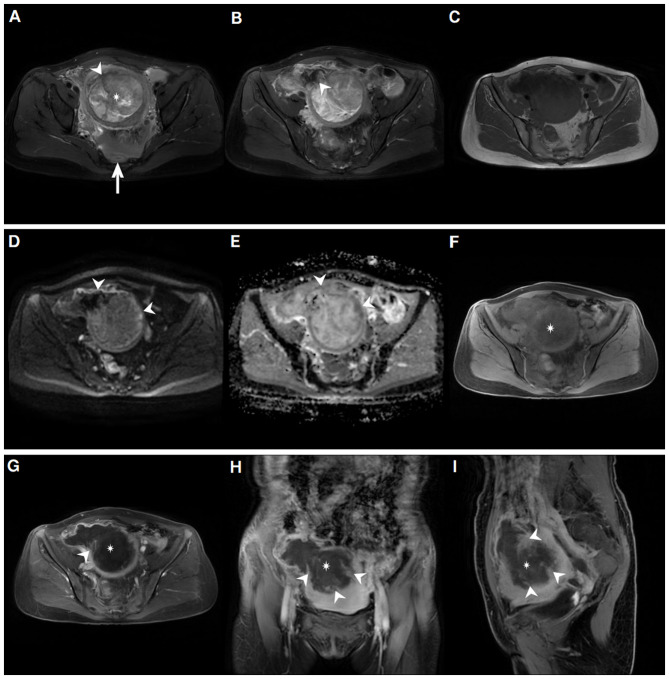

Case description: A 52-year-old woman presented at the clinic with right lower abdominal pain, persisting for over 5 days, significantly impacting her daily activities. Self-examination revealed a palpable abdominal mass. Ultrasonography identified an inhomogeneous echogenic mass within the uterus, initially suspected to be a uterine fibroid. Subsequent magnetic resonance imaging indicated uterine fibroids with tumor rupture and bleeding. The pathological assessment confirmed low-grade ESS. The patient underwent a total hysterectomy and double adnexectomy and is now 4 months postoperative and surviving well.